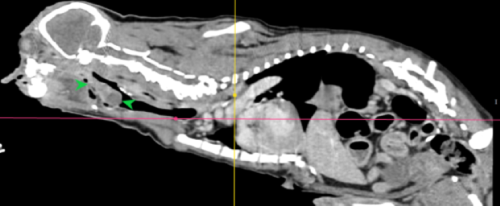

• 慢性咳嗽 支氣管肺炎 綠膿桿菌 電腦斷層掃描

慢性咳嗽 支氣管肺炎 綠膿桿菌 電腦斷層掃描